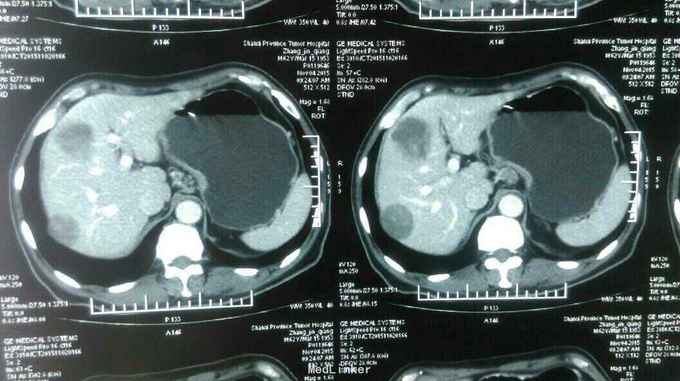

患者:男,62岁,主 诉:残胃癌多发转移化疗后,恶心呕吐5月余。 现病史:患者于2014年9月份自觉进食后上腹部饱胀感,就诊于忻州市人民医院,胃镜提示:胃大部切除术后,吻合口大弯侧粘膜隆起,充血,水肿,伴糜烂,质 脆,易出血,于2014年9月23日就诊于中国医学科学院肿瘤医院,诊断残胃癌,中分化腺癌,全腹部示CT提示:胃远端呈术后改变,吻合口扩张不良,吻合口壁厚,吻合口周围、胃左区新发现多发不均匀结节,大者短径约1.6cm;腹腔肠系膜根部、腹膜后多个小淋巴结;肝脏新出现多发结节,大者直径约1.5cm,考虑转移,盆腔少量积液。于2014年11月15日行XELOX方案化疗一周期,具体用药:奥沙利铂150mg,d1希罗达1500mg早 2000mg晚d1-d10,14天重复一次。后于忻州市人民医院2014年11月至2015年01月给予XELOX 方案化疗全身化疗5周期,化疗第二周期后,患者上腹部饱胀感减轻。于2015年3月12日就诊山西省肿瘤医院,全腹部CT提示胃腔缩小,残胃壁增厚,最后处约1.9cm,,残胃下方系膜内一枚囊性结节,大小约2.9X2.3cm,转移不除外:肝脏S8段一枚低密度灶,大小约为0.6X0.4cm;右肺中叶结节,大小约为1.6X1.4cm,肝脏S8段动脉期环形强化结节,考虑转移,右肺中叶炎性病变,继续给予行XELOX方案化疗2周期(奥沙利铂200mg,卡培他滨1.5g/次,2次/日,共14天)。因骨髓抑制明显,于2015年5月4日入该院后给予卡培他滨化疗一周期(卡培他滨2g/次,2次/日,共计14天)。2015年6月10日入该院复查CT提示肝内多发低密度影,部分新增,右肺中叶局限性肺不张,纵膈内多发小淋巴结,给予更换TP方案化疗一周期(多西他赛120mg,顺铂90mg),治疗结束于6月25日出院。出院后患者间断出现恶心、呕吐,于7月13日入该院复查胸腹部CT:残胃壁局部略变薄;头颅核磁未见异常。患者体质较差,不能耐受化疗,于7月21日始口服阿帕替尼250mg/日治疗。后患者间断出现恶心、呕吐,呕吐物为胃内容物,8月底患者停服阿帕替尼。9月8日入该院复查提示:肝脏多大转移增大,患者恶心、呕吐明显,予以留置鼻饲营养管,行EOF化疗一周期,共计用药:奥沙利铂150mg,表柔比星50mg,氟尿嘧啶3.0g,化疗所致骨髓抑制Ⅱ度。2015-11-02再次入住山西省肿瘤医院给予康莱特静点等对症治疗9天。目前患者每日鼻饲饮食后呕吐7-8次,每次呕吐量约40-50ml左右,全身疲软,精神食欲差,睡眠尚可,大便3-4日一次,较干结,小便基本正常,近3月体重下降约5kg。 既往史:既往患者高血压病史15年余,最高血压达180/100mmHg,平素口服尼福达片1片/日降压治疗,血压控制尚可;2型糖尿病10年余,曾皮下注射诺和灵30R控制血糖,近1月因进食量减少,已停用胰岛素治疗;40年前因“十二指肠穿孔”行胃大部除术;5年前山西医科大学第二医院确诊右半结肠癌行右半结肠切除术;10年前曾行阑尾切除术

诊断: 中医诊断: 胃癌 痰气交阻 西医诊断:残胃癌 中分化腺癌 浸润型 Lauren分型:肠型 肝转移 胃周 腹腔淋巴结转移 多疗程化疗后 空肠营养管植入术后: 呕吐原因待查 中度贫血 右半结肠癌(术后、化疗后) 2型糖尿病 治疗:入院给予查腹部立位片未见液气平面,给予止吐,输血纠正贫血,营养支持,中医中药扶助正气治疗,行动脉介入化疗药灌注(奥沙利铂150mg+氟尿密啶0.75g),肝转移灶(吡柔比星20mg+碘化油6ml)栓塞治疗。